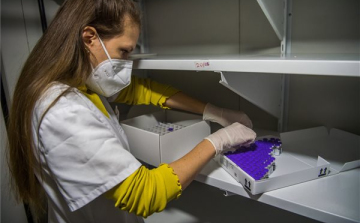

Felső korhatár nélkül alkalmazzák az AstraZeneca vakcinát Romániában

Romániában eltörölték az eddigi 55 éves korhatárt, és a továbbiakban valamennyi, 18. életévét betöltött felnőtt megkaphatja a koronavírus elleni AstraZeneca vakcinát

A beoltottak száma meghaladta a fertőzöttekét Romániában

Romániában a koronavírus ellen beoltottak száma szombaton meghaladta a járvány kezdete óta beazonosított fertőzöttekét.

Tovább halasztják a már előjegyzett személyek beoltását Romániában

Romániában tovább halasztják a társadalom számára kiemelten fontos munkát végző foglalkoztatási csoportok már előjegyzett tagjainak a beoltását

Ellenőrzik az oltóhelyeket a jogosulatlan páciensek kiszűrésére Romániában

Vlad Voiculescu román egészségügyi miniszter ellenőrzéseket rendelt el az oltóközpontokban, miután kiderült, hogy több mint ezerháromszáz személy jogosulatlanul, soron kívül oltatta be magát.